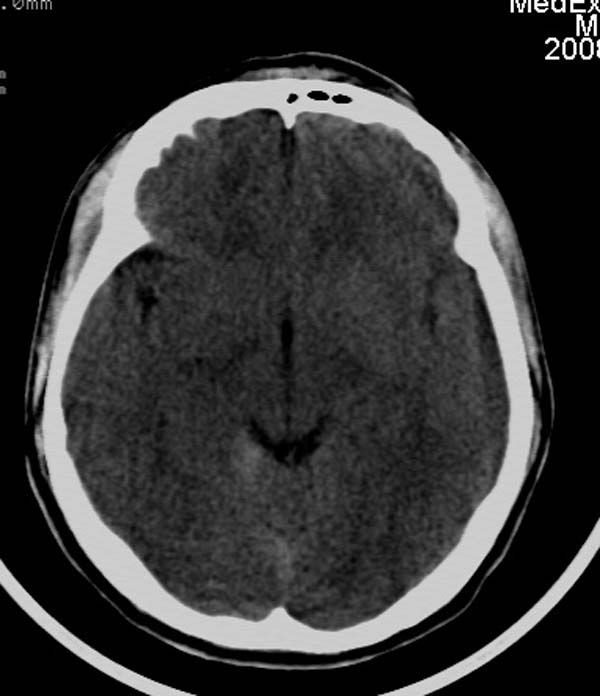

患者,男,24岁。头面部外伤后意识障碍1小时。

小脑幕缘密度增高,考虑有少量出血,建议复查

考虑右侧天幕缘少量蛛网膜下腔出血;建议:必要时复查。

1)考虑少量蛛网膜下腔出血;建议:必要时复查。2)桥前池及左侧环池表皮样囊肿可能。建议:行mri检查。

考虑右侧天幕缘区域少量蛛网膜下腔出血。

当ct表现不明显,临床症状相当明显时,建议mri+dwi序列除外弥漫性轴索损伤之可能。

一侧密度增高,是否考虑为硬膜下血肿,前额血肿真好对冲伤,桥小脑脚增宽建议进一步检查